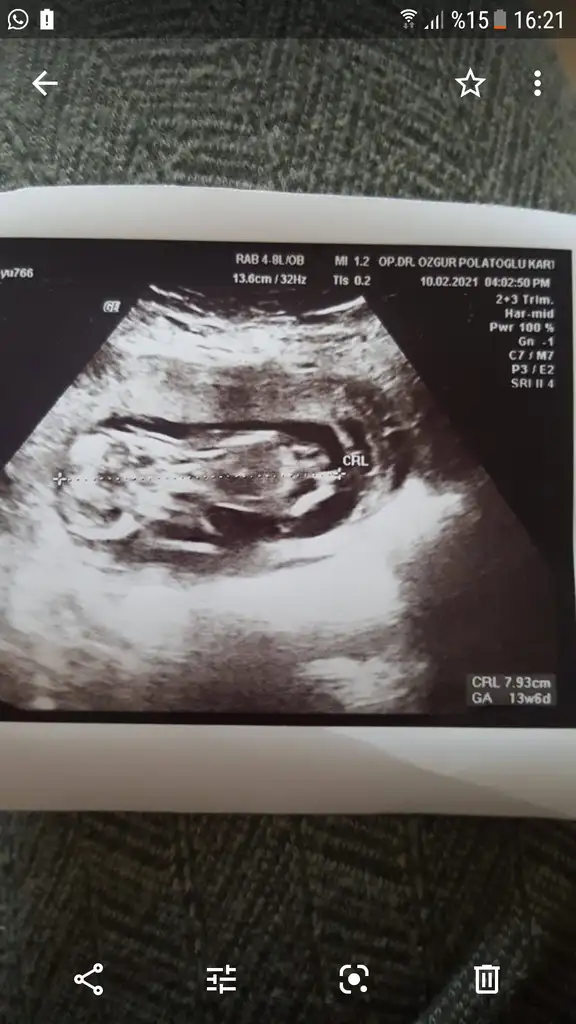

12. Hafta karın ultrason lütfen tahminnKız sanki emin olamadım 12-13 hafta olursa paylaşın![]()

Bu bebiş de kız benceBanada tahminde bulunur musunuz 12+2